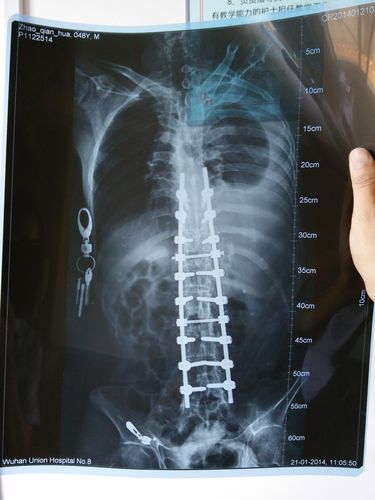

请问您有最近的片子吗?如果有可以给我传来

具体分析您的病情严重程度,以及下一步该怎么控制、治疗等,会给您一个满意的答复有些人一听到